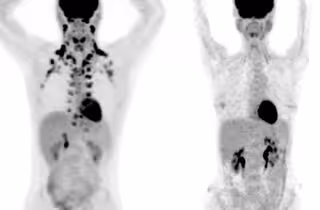

En estas tomografías, la persona de la izquierda tiene abundante grasa marrón alrededor del cuello y la columna cervical. La persona de la derecha no tiene grasa marrón detectable.

En estas tomografías, la persona de la izquierda tiene abundante grasa marrón alrededor del cuello y la columna cervical. La persona de la derecha no tiene grasa marrón detectable. - ANDREAS G. WIBMER Y HEIKO SCHDER